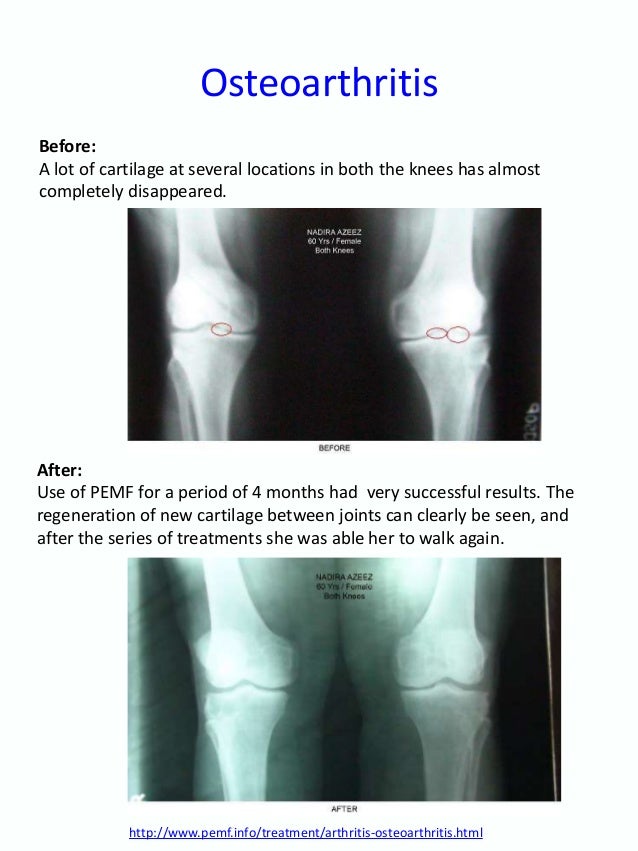

Arthritis - Wikipedia